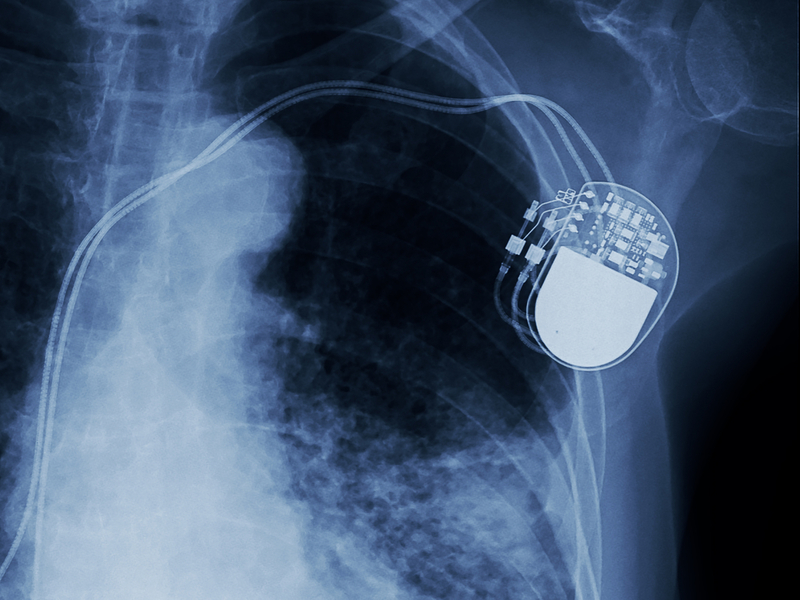

A CRT-D is a special device for heart failure patients who are also at high risk for sudden cardiac death. While functioning like a normal defibrillator (called an implantable cardioverter defibrillator, or ICD) to treat slow heart rhythms and life-threatening fast heart rhythms, a CRT-D device also delivers small electrical impulses to the left and right ventricles to help them contract at the same time. This helps the heart pump more efficiently.